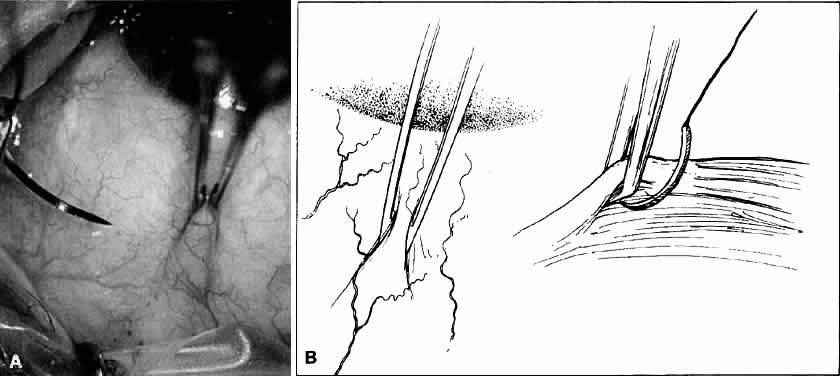

Scissors also may be used surgically by opening the blades. This maneuver is employed primarily during blunt dissection (Fig. 26). In this procedure, the surgeon is cutting with the blade tips. Sharp points can force their way through tissue, whereas blunt tips act as a spatula and do not damage surrounding structures. When the surgeon dissects a conjunctival flap or into the sub-Tenon's space, blunt dissection is preferred. In addition, should the surgeon need to avoid disturbing the flaps (or a buttonhole), such as a conjunctival flap for a glaucoma procedure, the surgeon should not use scissors with sharp tips for blunt dissection. However, when the surgeon is working in an area that is scarred as a result of previous surgery, the use of sharp tips may be necessary.

Fig. 26. The sharp points of scissors are forcing their way through the subconjunctival space. Opening the scissors will result in blunt dissection of the subconjunctival space.

DISSECTING A FORNIX-BASED CONJUNCTIVAL FLAP

When a fornix-based conjunctival flap is dissected, several basic surgical principles are used. Ideally, there is a preexisting surgical plane through which the surgeon can use blunt dissection to separate the tissue. For the beginning surgeon, dissection of the surgical plane may be aided by injecting a local anesthetic or balanced salt solution into the subconjunctival space such that the force of injection of the fluid dissects the potential surgical plane (Fig. 38). The anatomy of the insertion of both the conjunctiva and Tenon's capsule must be familiar to the surgeon because the conjunctiva inserts more anteriorly than Tenon's capsule. These two layers may be dissected individually or together off the limbus. Some surgeons prefer to dissect these layers individually because this method allows for a cleaner dissection, with use primarily a 0.12-mm tissue forceps and blunt Westcott scissors. First, make the initial incision radial to the limbus and then use blunt dissection to separate the potential space between the conjunctival insertion and the insertion of Tenon's capsule. The conjunctiva is removed from the cornea with sharp dissection. The force applied to the scissors is toward the center of the cornea to ensure that the conjunctiva is dissected off at the corneal insertion. Tenon's capsule is picked up with the 0.12-mm forceps and incised. With blunt dissection, using Westcott scissors, Tenon's capsule is bluntly dissected from the globe by opening the scissors. The insertion of Tenon's capsule is incised by sharp dissection. Again, the force applied to the scissors is toward the center of the cornea. The beginning surgeon may tend to leave strands of Tenon's capsule on the limbus. Doing so may interfere with tying of sutures and burying of surgical knots because the small Tenon's fibers may become incorporated into the surgical knot, making it difficult to rotate the suture.